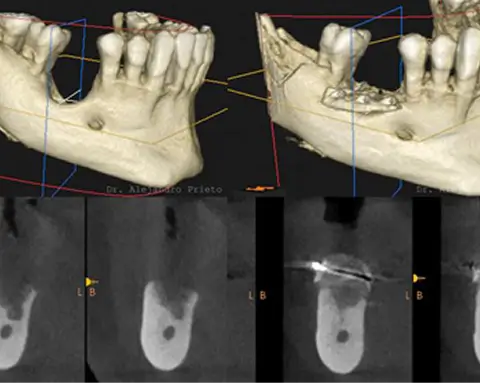

Regeneración ósea mediante técnicas avanzadas para aumentar volumen y permitir la colocación de implantes incluso en casos complejos. Máxima precisión y estabilidad asegurada.

Sí. El Dr. Alejandro Prieto es conocido a nivel internacional por su experiencia en implantología avanzada, incluyendo casos con pérdida ósea severa y situaciones clínicas complejas. Su trabajo se basa en una planificación minuciosa mediante el uso de las útimas técnicas digitales, combinando resultados de alta estética natural. El Dr. Alejandro Prieto recibe pacientes de todo España y del mundo para solucionar casos complejos de implantología.

Sí. En Alejandro Prieto Dental se realizan técnicas avanzadas de regeneración ósea que permiten colocar implantes incluso en pacientes con poco hueso. Cada caso se estudia de forma individual y se planifica la técnica más adecuada; desde técnicas de regeneración ósea hasta el uso de implantes dentales diseñados para pacientes con falta de hueso dental.